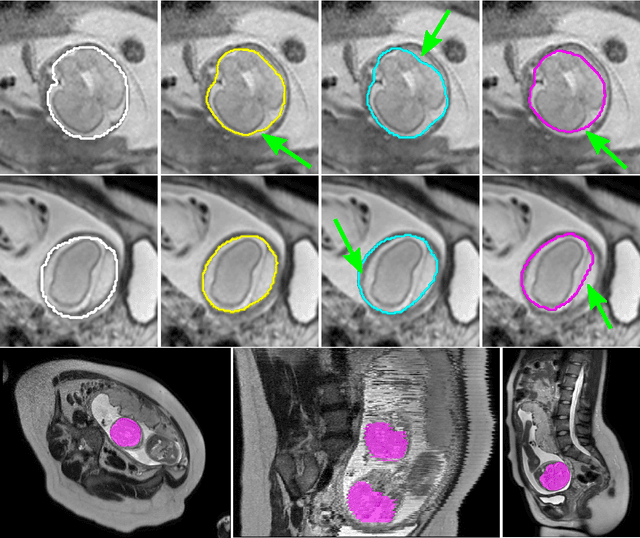

Abstract:The availability of training data for supervision is a frequently encountered bottleneck of medical image analysis methods. While typically established by a clinical expert rater, the increase in acquired imaging data renders traditional pixel-wise segmentations less feasible. In this paper, we examine the use of a crowdsourcing platform for the distribution of super-pixel weak annotation tasks and collect such annotations from a crowd of non-expert raters. The crowd annotations are subsequently used for training a fully convolutional neural network to address the problem of fetal brain segmentation in T2-weighted MR images. Using this approach we report encouraging results compared to highly targeted, fully supervised methods and potentially address a frequent problem impeding image analysis research.